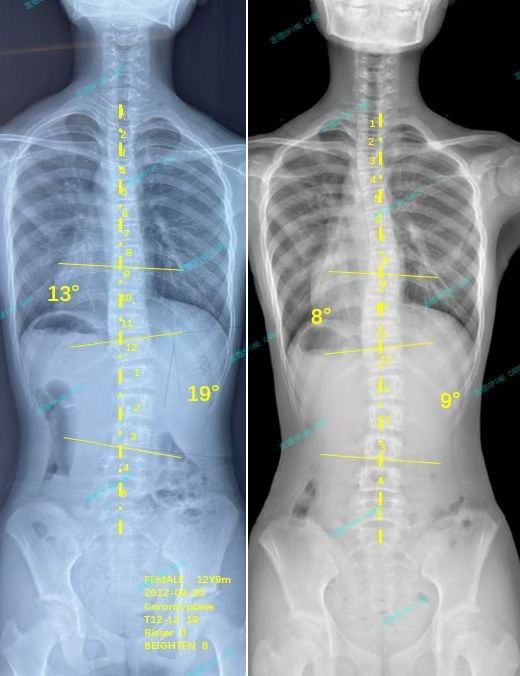

我是瑶瑶,右腰弯从19度回到9度,高低肩也消失了!

案例主人:瑶瑶 发现侧弯年龄:12岁 侧弯情况:Cobb角度19度

我是瑶瑶,今年12岁,一个热爱画画和奔跑的普通女孩。直到今年夏天的一次体检,我的生活里多了一个陌生的词汇——“脊柱侧弯”。诊断书上的数字冰冷而清晰:右腰弯19度,旋转10度。

一个月左右的时候我就已经看到了自己的高低肩已经基本对称了,直到三个月后再次拍片,我的19度右腰弯降低到了9度,旋转也从10度降到了5度,身体看起来明显正了很多,杨博士也说我的身体已经趋近中线了,体态好了很多,我和妈妈都非常开心。我还会继续训练,维持住这样的成果,直到脊柱侧弯没有再加重的可能。

About a month later, I could already see that my high and low shoulders were basically symmetrical. Until three months later, my 19-degree right waist bend was reduced to 9 degrees, and the rotation was also reduced from 10 degrees to 5 degrees. My body looks obviously much more upright. Dr. Yang also said that my body was approaching the midline and my posture was much better. My mother and I were very happy. I will continue to train and maintain this result until there is no possibility of scoliosis getting worse.